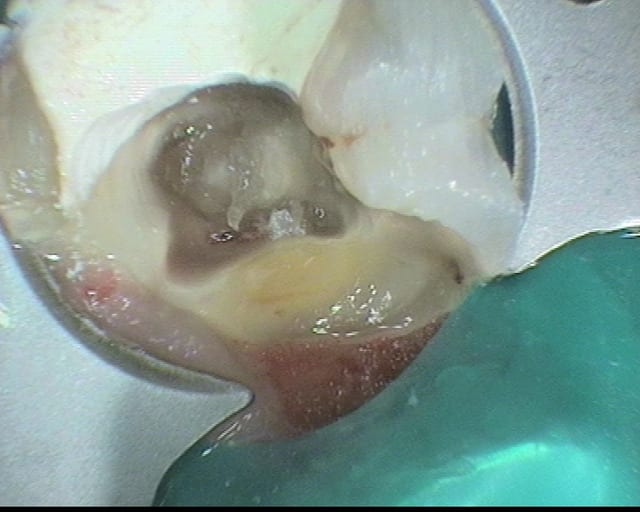

Je profite d'une pause pendant les vacs pour mettre en ligne l'ultime endo avant les vacances estivales (37).

Première effraction du plancher depuis mon diplôme en 2005.

L’éviction des pulpolithes a été réalisée par ultrason. J'ai suivi une coloration entre ce que je pensais être de la dentine réactionnelle et le reste de chambre pulpaire comblée par un gros pulpolithe.

J'ai placé un MTA, CVI par dessus. Je reprends l'endo en septembre.

A votre avis, quels éléments m'ont induit en erreur ? Sur ce type de cas, avez-vous une approche différente ?